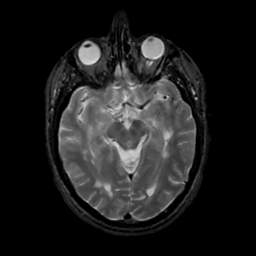

MR Study #10, April 28, 1991 -- Slice #21